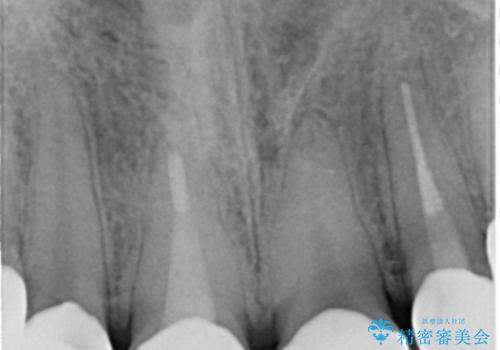

精査したところ、ほとんどの歯が保険内のレジンで充填されており、咬み合わせも悪く咬合していない歯もありました。

虫歯をしっかりと治療したのち、オールセラミッククラウンによる補綴治療を行いました。